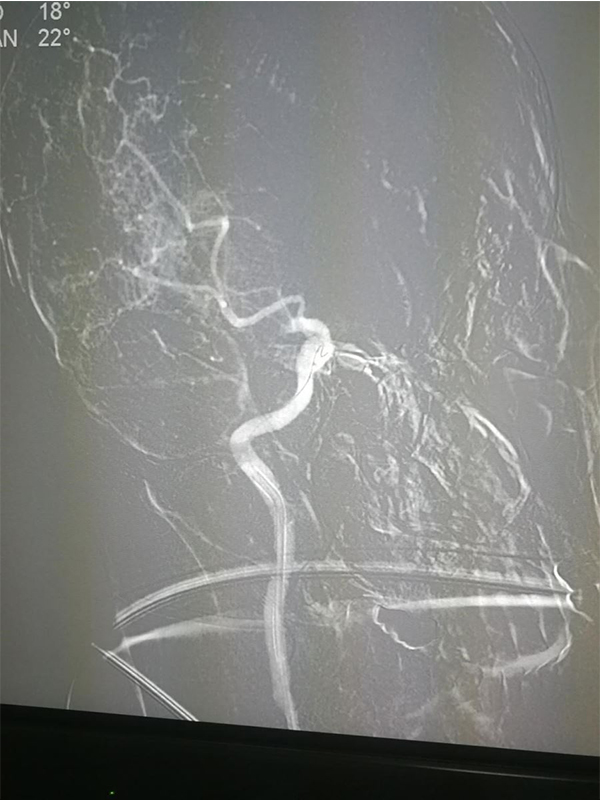

Solitaire 6mm 20mm ( 4 5)

( 6)